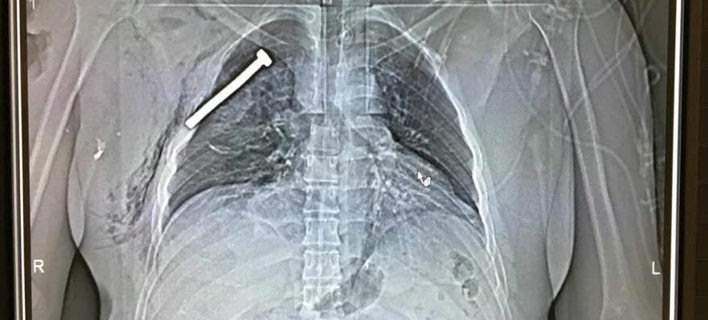

Επίθεση Βρυξέλλες: Ακτινογραφία ενός εκ των τραυματιών επιβεβαιώνει τα καρφιά στις βόμβες (φωτό)

«Χτύπησαν» σε πολυσύχναστα μέρη, το αεροδρόμιο και σταθμό του μετρό των Βρυξελλών και είχαν σχεδιάσει τις βόμβες τους έτσι ώστε να προκαλέσουν όσο περισσότερες απώλειες ήταν δυνατόν. Μία ακτινογραφία ενός εκ των δεκάδων τραυματιών από τις βομβιστικές επιθέσεις στη βελγική πρωτεύουσα επιβεβαιώνει με ανατριχιαστικό τρόπο την αποκάλυψη των αρχών ασφαλείας, ότι οι τρομοκράτες είχαν βάλει […]

Καρφιά και βίδες στις βόμβες για να προκαλέσουν εκατόμβη στις Βρυξέλλες

Μια ανατριχιαστική αποκάλυψη έκαναν οι αρχές του Βελγίου, λίγες ώρες μετά τη διπλή βοβμιβαστική επίθεση σε αεροδρόμιο και σταθμό μετρό που προκάλεσε το θάνατο 34 ανθρώπων και τον τραυματισμό 187. Στα απανθρακωμένα και διαμελισμένα θύματα αλλά και στα σώματα τραυματιών από το μακελειό στις Βρυξέλλες, στο αεροδρόμιο των Βρυξελλών, Ζaventem, οι αρχές βρήκαν υπολείμματα από […]